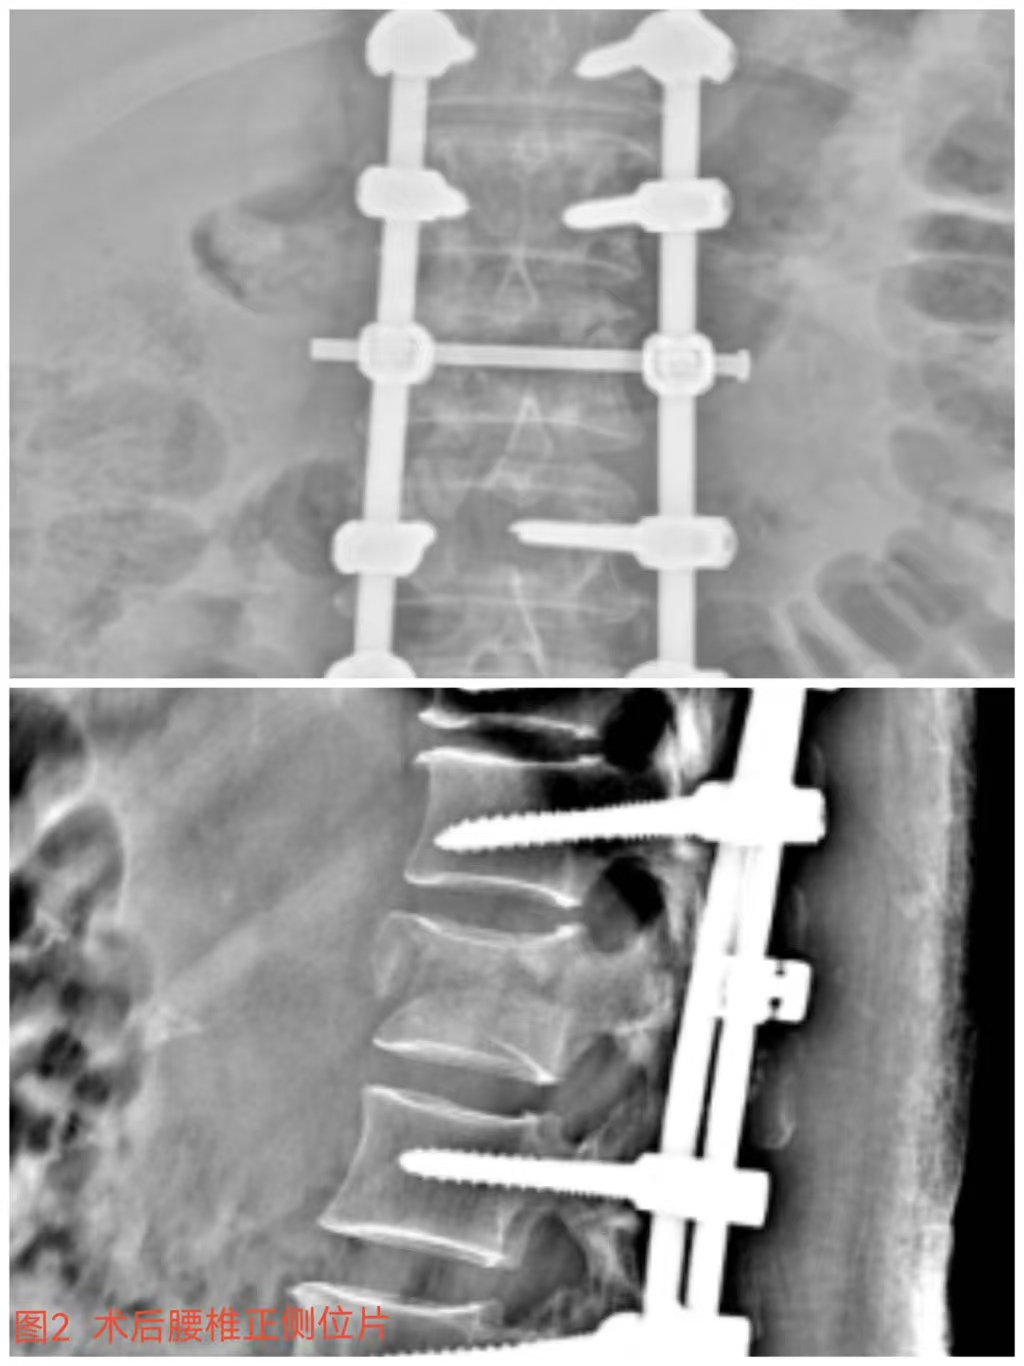

俞德亮副主任醫(yī)師深知病情的嚴(yán)重性,拖得時(shí)間越久,脊髓神經(jīng)損傷癥狀越難以恢復(fù),必須把握住早期減壓手術(shù)的關(guān)鍵時(shí)間窗,緊急帶領(lǐng)創(chuàng)傷骨科醫(yī)師團(tuán)隊(duì)對(duì)該病情進(jìn)行討論、制定手術(shù)方案,并成功為患者急診行“L1椎體爆裂性骨折伴截癱切開(kāi)椎板切除+椎管探查減壓+骨折復(fù)位釘棒系統(tǒng)內(nèi)固定術(shù)(圖2)”,該手術(shù)精確解除對(duì)脊髓神經(jīng)的壓迫,并通過(guò)椎弓根螺釘內(nèi)固定系統(tǒng)對(duì)受損的腰椎提供穩(wěn)固的支撐,為后期的康復(fù)創(chuàng)造了良好的條件。